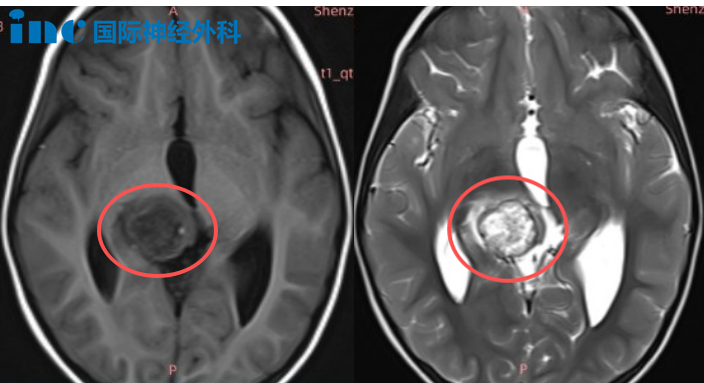

谁能预料,这个活泼爱笑的孩子,右侧丘脑深处存在一个22×21×19毫米的肿瘤,病灶已经邻近中脑区域并导致中脑导水管受压。这次摔跤意外发现的肿瘤并未给果果带来明显临床症状,但影像学检查显示清晰病灶和脑积水迹象,潜在危险性不容忽视。

巴教授明确指示:"MRI检查显示患儿脑积水已相当严重,虽然目前没有症状,但脑积水随时可能造成危险,推迟手术并非明智选择。"

他进一步解释,尽管肿瘤位置深在,但通过枕部与小脑之间的自然解剖间隙,存在一个理想的手术通道,能够安全抵达病灶区域。"我们的治疗目标是实现肿瘤全切除。"